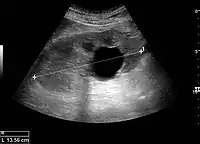

Renal ultrasonography of a simple renal cyst with posterior enhancement.

Renal cyst as seen on abdominal ultrasound